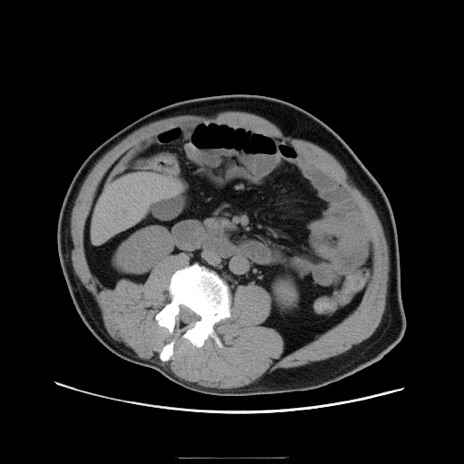

冠状断像

【症例】50歳代男性

【主訴】腹痛

【現病歴】AVMからの被殻出血のため回復期リハ病棟入院中。 本日午後3時頃急に下腹部痛が出現した。

【既往歴】AVM、被殻出血、虫垂炎、高血圧

【身体所見】意識晴明、左半身不全麻痺、会話の理解は良好、36.5°C、腹部:膨隆、全体に板状硬、下腹部正中に圧痛点あり、反跳痛-、筋性防御不明、右下腹部にope scar

【データ】WBC 9400、CRP 0.06